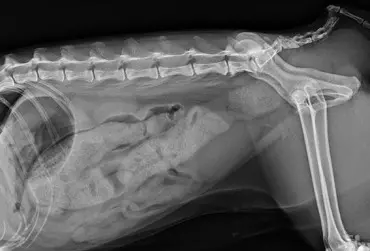

Torbiel pierwotna jest rzadką wadą rozwojową występującą u człowieka, psa, kota i konia. W niniejszym artykule opisano przypadek torbieli pierwotnej jelita prostego u dziewięcioletniego kota rasy Manx, u którego występowały przewlekłe zatwardzenia. W badaniu rektalnym i radiograficznie stwierdzono obecność miękkiego guza dogrzbietowo i bocznie od jelita grubego. Badaniem ultrasonograficznym i w tomografii komputerowej uwidoczniono dobrze odgraniczoną, cienkościenną torbiel, częściowo zamykającą światło kanału miednicy. Torbiel usunięto chirurgicznie z dojścia okołoodbytowego. Nie stwierdzono połączenia torbieli ze ścianą prostnicy. Badanie histopatologiczne potwierdziło postawione podejrzenie torbieli pierwotnej. Po wykonanym zabiegu objawy kliniczne całkowicie ustąpiły.